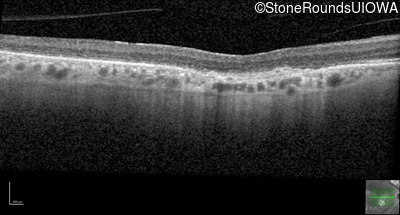

Optical Coherence Tomography - Left - 20/100

Exemplar / OCT Stack